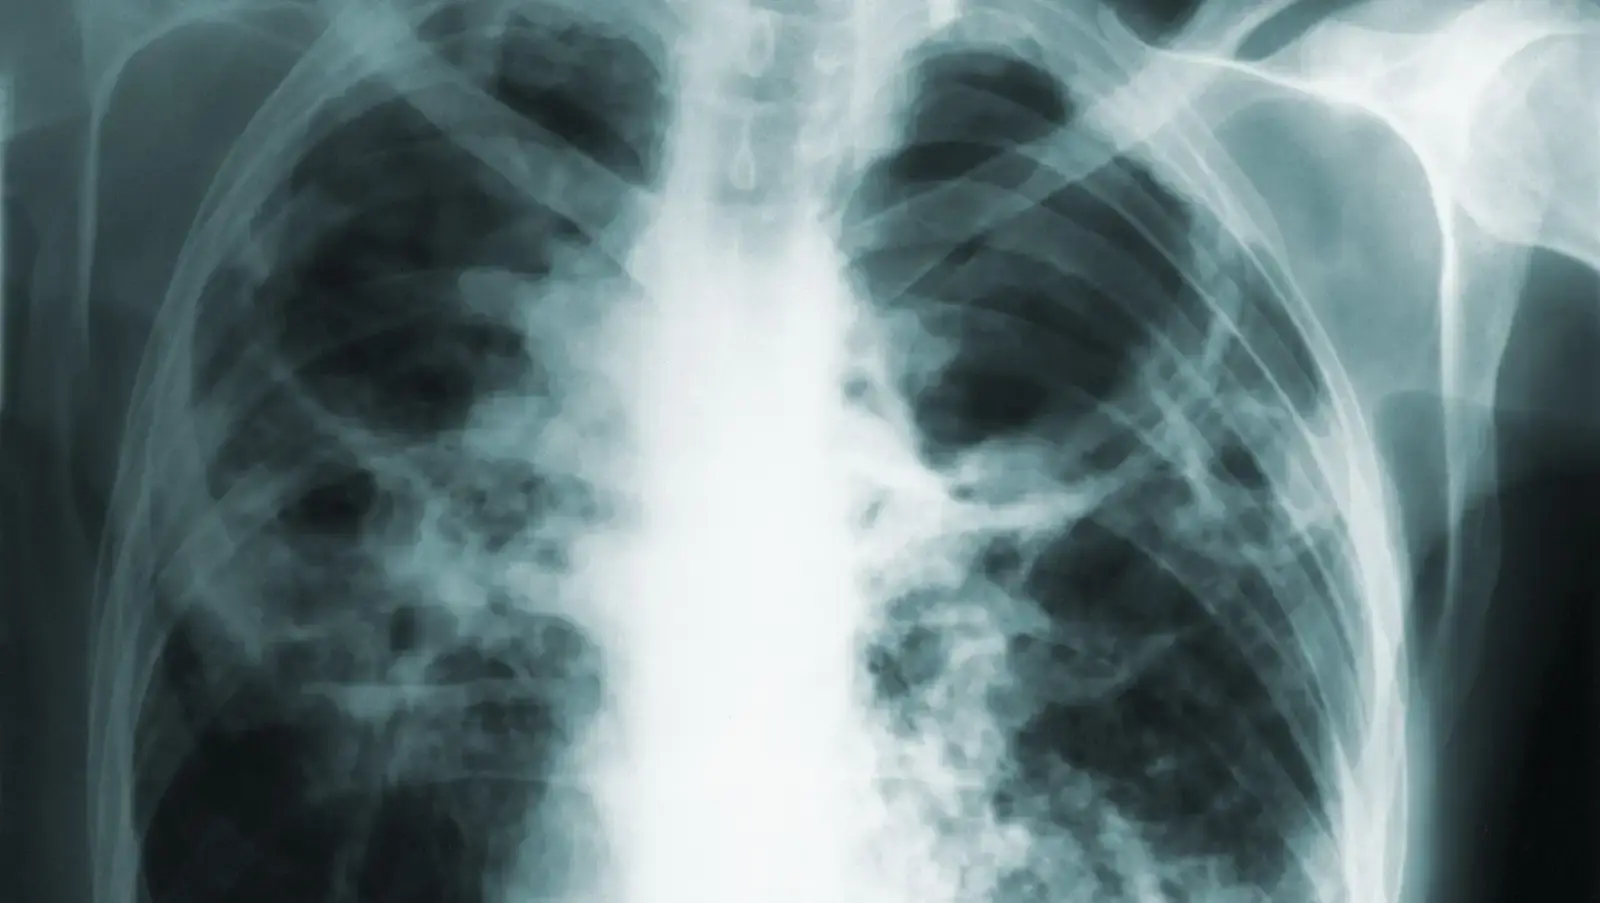

Туберкулез, или туберкулез, вызывается микобактериями туберкулеза. Многие люди, инфицированные бактериями туберкулеза, не заболевают, и часто инфекция переходит в латентное состояние, когда уровни бактерий остаются низкими, а люди не болеют и не заразны для других. Однако, если ее не лечить, инфекция может вновь появиться и даже стать опасной для жизни, особенно у людей с ослабленной иммунной системой. Активный туберкулез обычно поражает легкие, вызывая респираторные симптомы, но инфекция может мигрировать и в другие части тела.

По данным The News Tribune, женщина нарушила первоначальное постановление суда и последующие, полученные департаментом здравоохранения. Но последняя капля, похоже, произошла в январе этого года. В ходатайстве, поданном 11 января, ведомство утверждало, что женщина недавно попала в автомобильную аварию. Днем позже она обратилась за помощью в отделение неотложной помощи по поводу боли в груди и получила рентгеновские снимки. Сообщается, что женщина не сообщила ER о своем статусе туберкулеза, потенциально подвергая их и других инфекции. Ее неразглашение даже заставило персонал предположить, что ее симптомы могли быть вызваны раком легких. И женщина, как сообщается, также дала положительный результат на covid-19 в то же время.